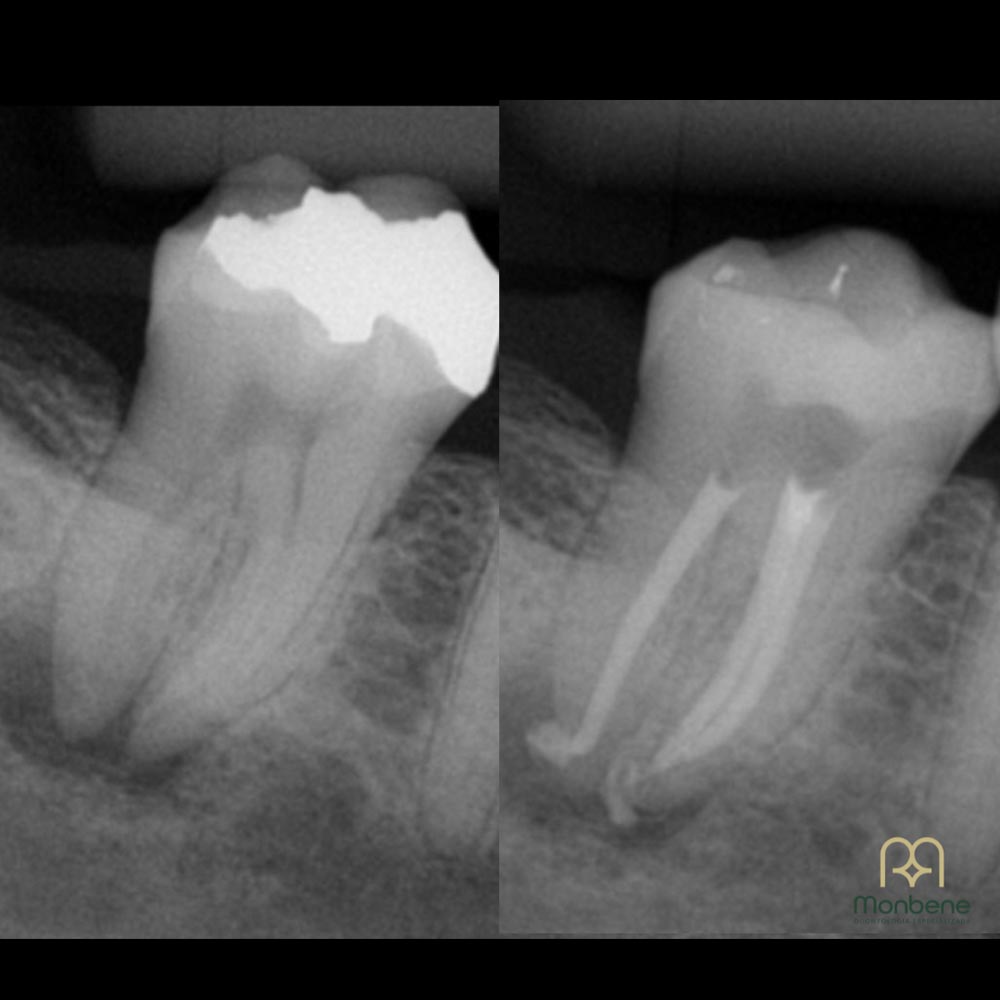

A endodontia é a especialidade da odontologia responsável pelo tratamento do canal do dente. Ela atua quando a polpa dental — a parte interna onde ficam nervos e vasos sanguíneos — sofre inflamação ou infecção, geralmente causada por cárie profunda, fratura ou trauma. O objetivo é preservar o dente, eliminando a dor e devolvendo sua função.

O uso do microscópio odontológico trouxe mais precisão e segurança ao tratamento de canal.

Maior visibilidade

das estruturas internas do dente mesmo nos canais mais finos e difíceis de localizar;

Mais precisão

garantindo limpeza completa e reduzindo riscos de falhas;

Procedimentos mais conservadores

preservando ao máximo a estrutura saudável do dente;